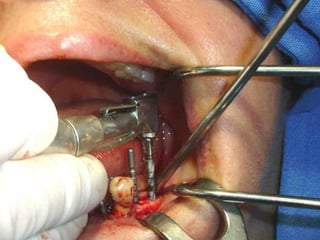

Arteria facial pinzadaArteria facial pinzada

Sierra de GigliSierra de Gigli

Luxación de hemimandíbulaLuxación de hemimandíbula

Plantilla flexible para dar forma previa al implante

Se respetó el cóndilo para anclar la prótesisSe respetó el cóndilo para anclar la prótesis

Plantilla flexible paradar forma previa al implante

Se respetó elcóndilo para anclar la prótesisSe respetó el cóndilo para anclar la prótesis